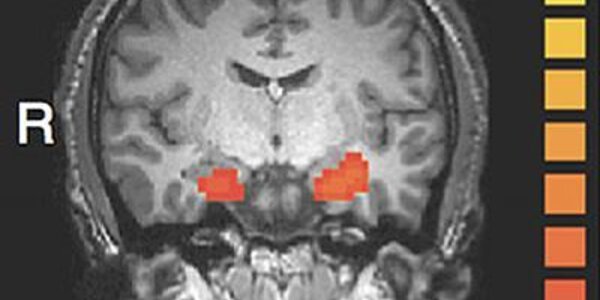

Gruseome Details Versus Evidence - The Brain Science Of Punishment Decisions

Issues of crime and punishment and vengeance and justice date back to time when people first gathered and in the last few years why people decide just punishment has captured the attention of psychologists and certainly defende attorneys.  A brain imaging study in Nature Neuroscience says it can identify the brain mechanisms that underlie our judgment of how severely a person who has harmed another should be punished. Specifically, the study looked at how the area of the brain changes when an act was believed to be intentional or unintentional. They found that the imaging is different…